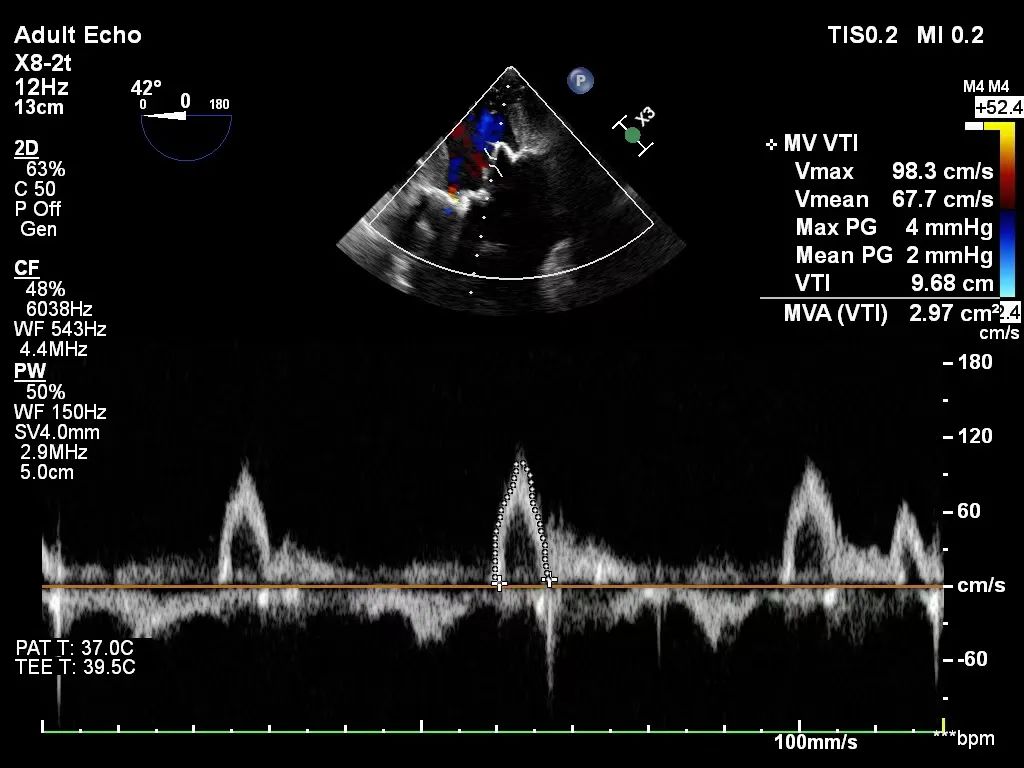

患者男性,68岁,主诉因“活动后胸闷、气促半年”入院,行心脏超声检查提示:主动脉瓣二瓣化畸形、狭窄 (重度)合并关闭不全(中-重度),二尖瓣狭窄并关闭不全(重度),左房明显增大。冠脉造影提示三支血管严重狭窄病变。吴钟凯教授经过周密的术前讨论与部署,联合麻醉科、手术室等多科室强大的协作实力,术中建立体外循环转机,首先完成冠状动脉旁路移植(LIMA-LAD,GSV-LCX; GSV-RCA);二尖瓣位植入M27佰迈思®限位可扩张二尖瓣生物瓣,主动脉瓣位置入A21佰迈思®限位可扩张主动脉瓣生物瓣。心超提示:冠心病CABG+DVR术后,人工主动脉瓣及人工二尖瓣功能良好,人工主动脉瓣测其平均压差5mmHg,人工二尖瓣测其平均压差3mmHg。瓣膜功能表现出色,患者术后恢复良好。